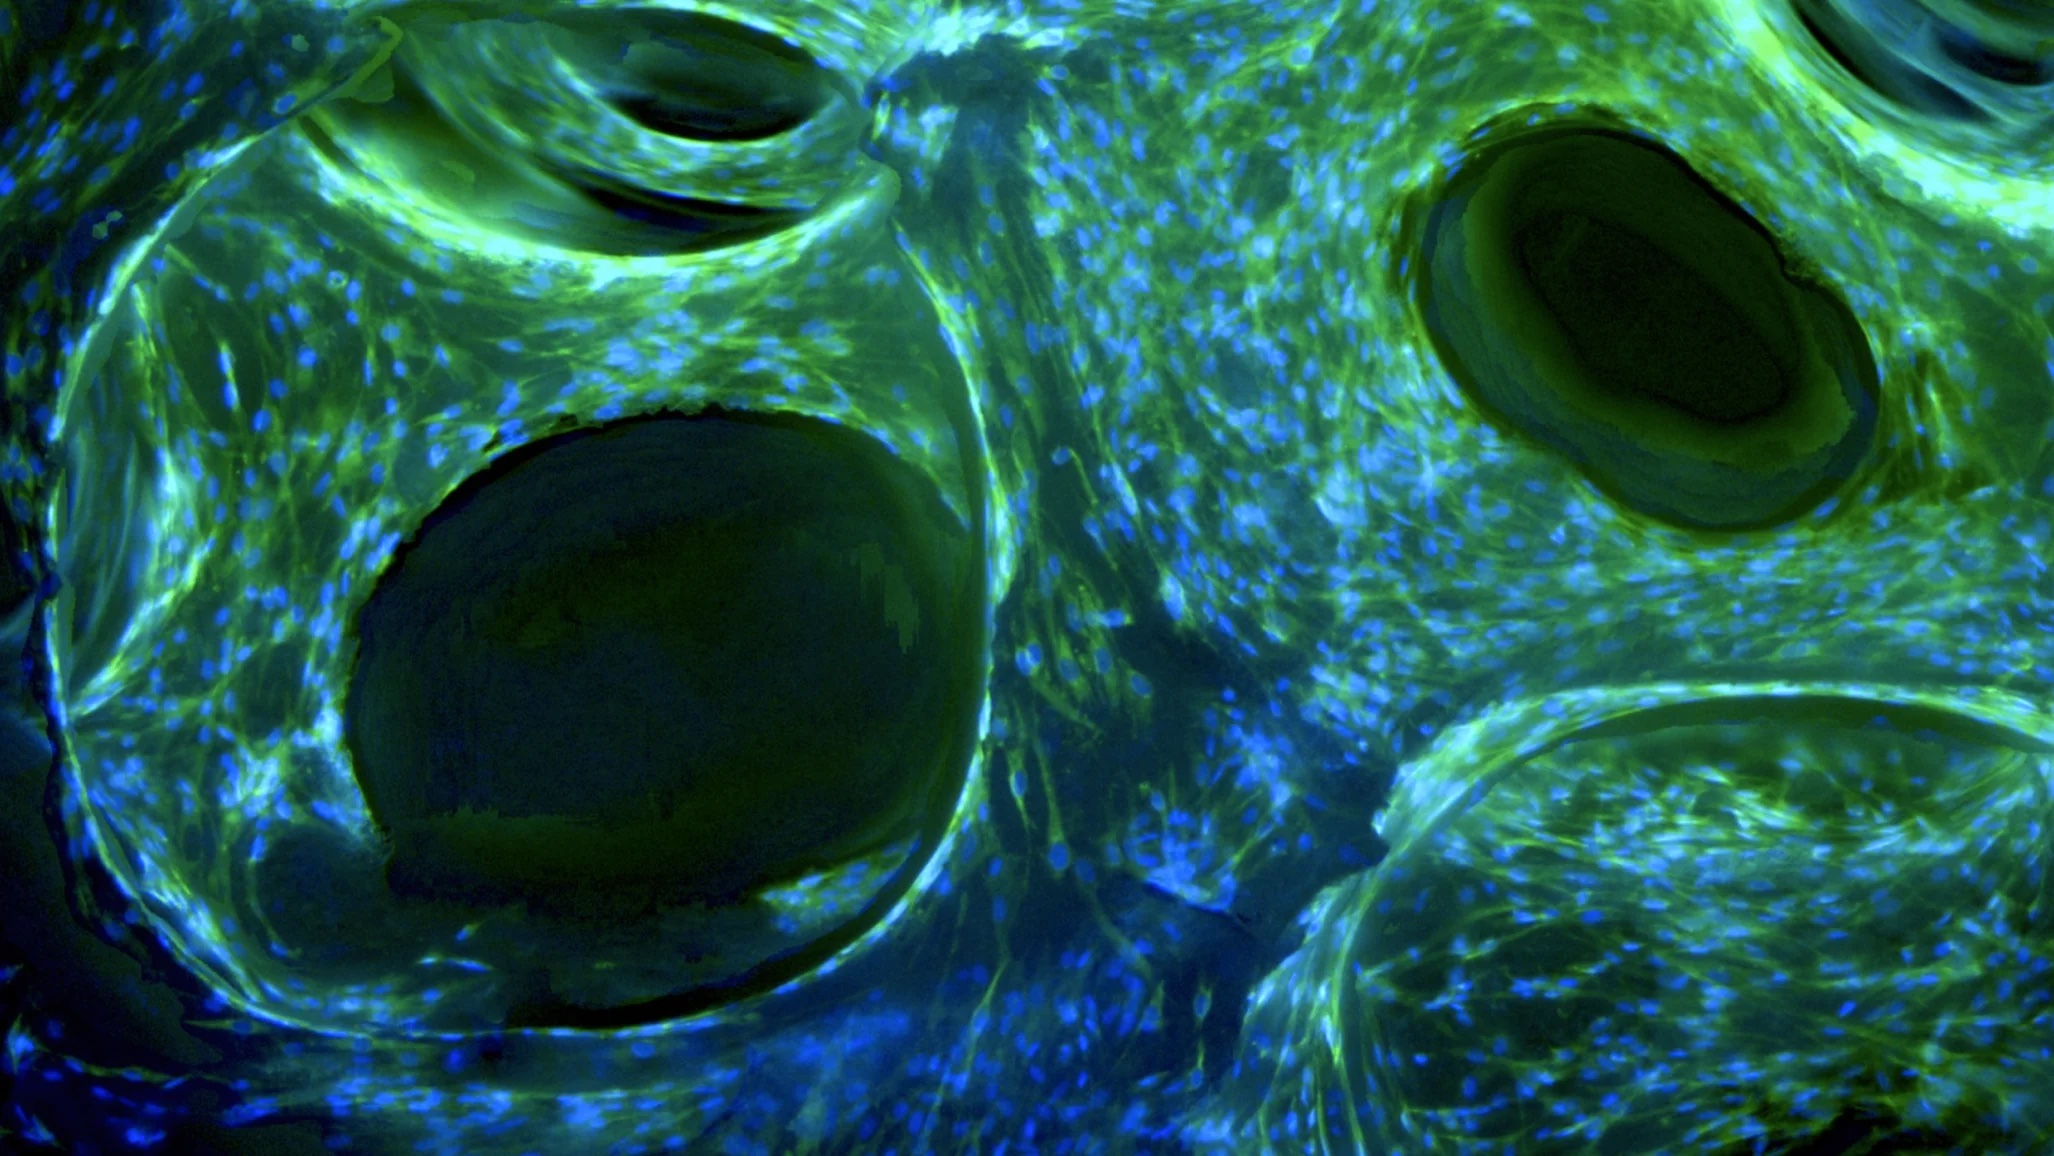

One of the more significant limitations of current synthetic bone grafts is insufficient cell migration into implanted bone grafts. In some cases, there is limited surface area for cell attachment, and in others, there is an insufficient supply of oxygen and nutrients for the frontage cell-line. Other products may be slow in increasing cell numbers inside the bone graft or may have a limited amount of blood vessel formation and blood circulation that assuages healthy cell growth. It is also not uncommon in cases of bone grafting for there to be slower or fewer cell differentiation. In all, these limitations correlate to the end result of poor bone regeneration and, in some cases, non-union between the new growth and the pre-existing bone.

In the same vein of thought of new bone growth, it is vital that implanted bone grafts are capable of providing mechanical integrity and nutrient support during the process of bone regeneration. A preemptive collapse of the graft could disrupt the healing process, and a lack of nutrients to migrating cells prevents healthy cell growth and the formation of capillaries and blood vessels. On a cellular level, the product should allow for ease of migration of cells, abundant surface for cell to anchor proper distribution, proliferation, and microenvironments for osteogenesis and angiogenesis. Additionally, bone grafts should be customizable to the specific needs of the patient undergoing a dental procedure or surgery and therefore more widely applicable to a variety of cases. OsteoGeneTM Tech strove to meet the criteria for an ideal synthetic bone graft with InRoad® spearheading the movement to more efficient alloplast products that overcome the limitations commonly seen for bone regeneration. InRoad®’s design meets all the qualifications to be considered an ideal bone graft and actually goes beyond simply meeting the minimum requirements. With its three-part structure, InRoad® has a superior sucking property compared to the top bone grafts available on the market today, which facilitates greater ease in cell migration and new bone growth at the site of application, and has no reported adverse effects during its testing period. At this current point in time, InRoad® is opening a new stage for bone grafts for both medical practitioners and patients alike.